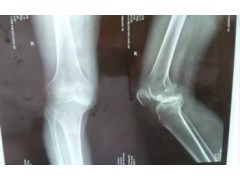

临朐腰间盘突出理疗 有保障的治疗颈肩腰腿痛推荐

以下文章详解临朐腰间盘突出理疗,中医治疗颈肩腰腿痛,治疗腰腿痛,山东按摩理疗的相关信息,请保存收藏。